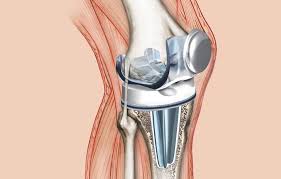

Prótesis de Rodilla

Reemplazo de la articulación dañada por una artificial para eliminar el dolor.